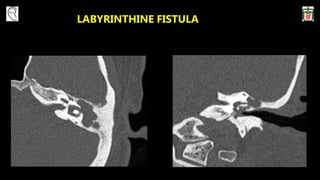

 LARGE LABYRINTHINE FISTULA

LABYRINTHINE FISTULA